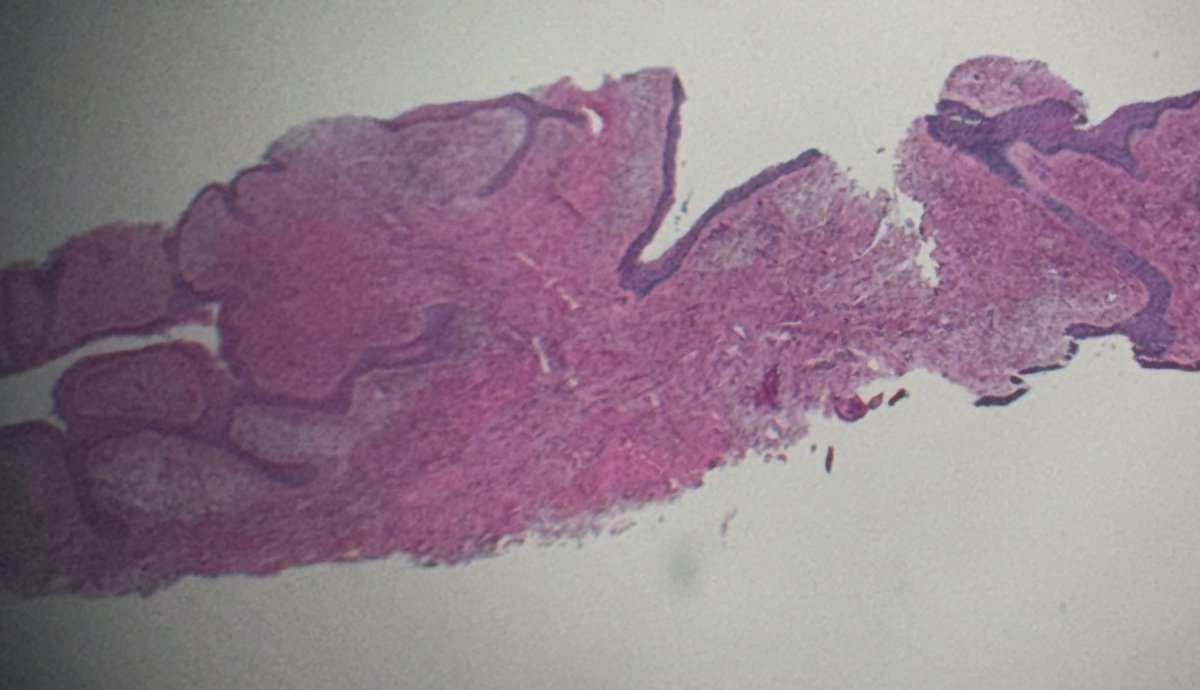

Our new work has just been published ๐Ÿ“„ "Sclerosing melanocytic tumors with MAP2K1 in-frame deletions and 15q gains: A distinctive pathway of nevogenesis with reproducible morphology." #dermpath #pathology Free access to the article here: https://t.co/7QXCZCcgVB